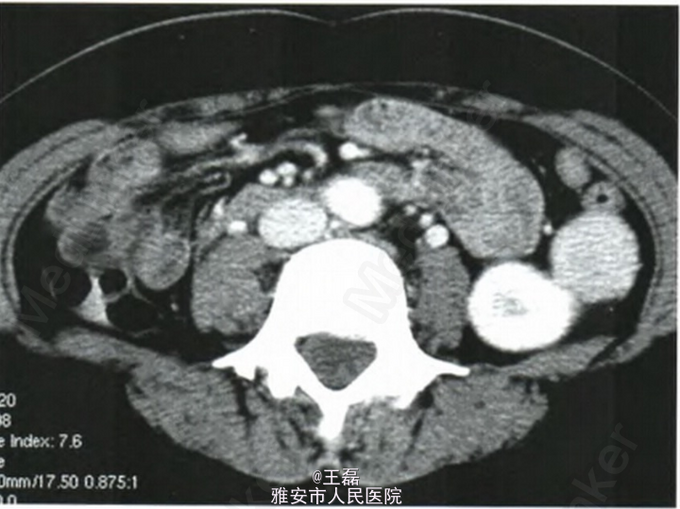

查体:腹部中线有一手术瘢痕,左上腹轻压痛,无其他阳性体征。 实验室检查:血糖类抗原1 856U/ml。 CT检查:胰腺体、尾部乏血供占位病变;脾脏术后缺如;左肾外上缘见一直径28 mm类圆形均匀软组织密度结节,轮廓清晰光整,基底宽,与肾皮质相连,平扫CT值57 HU,增强后动脉期明显均匀强化,CT值130 HU,静脉期持续均匀强化,CT值90 HU。

临床诊断为胰体尾癌。 全麻下行胰腺体尾部癌根治术。术中见肾外上缘直径约30 mm暗红色结节,有包膜,基底与肾包膜紧密粘连,局部数条小血管穿越。腹腔内大网膜、膈肌腹侧面、腹内壁有较多米粒至黄豆大小不等暗红色无蒂小结节灶散布,切除肾上结节及另4枚小结节灶送病理检查:(左肾)淋巴组织增生性病灶伴结节滤泡状结构,结合临床考虑为脾组织异位植